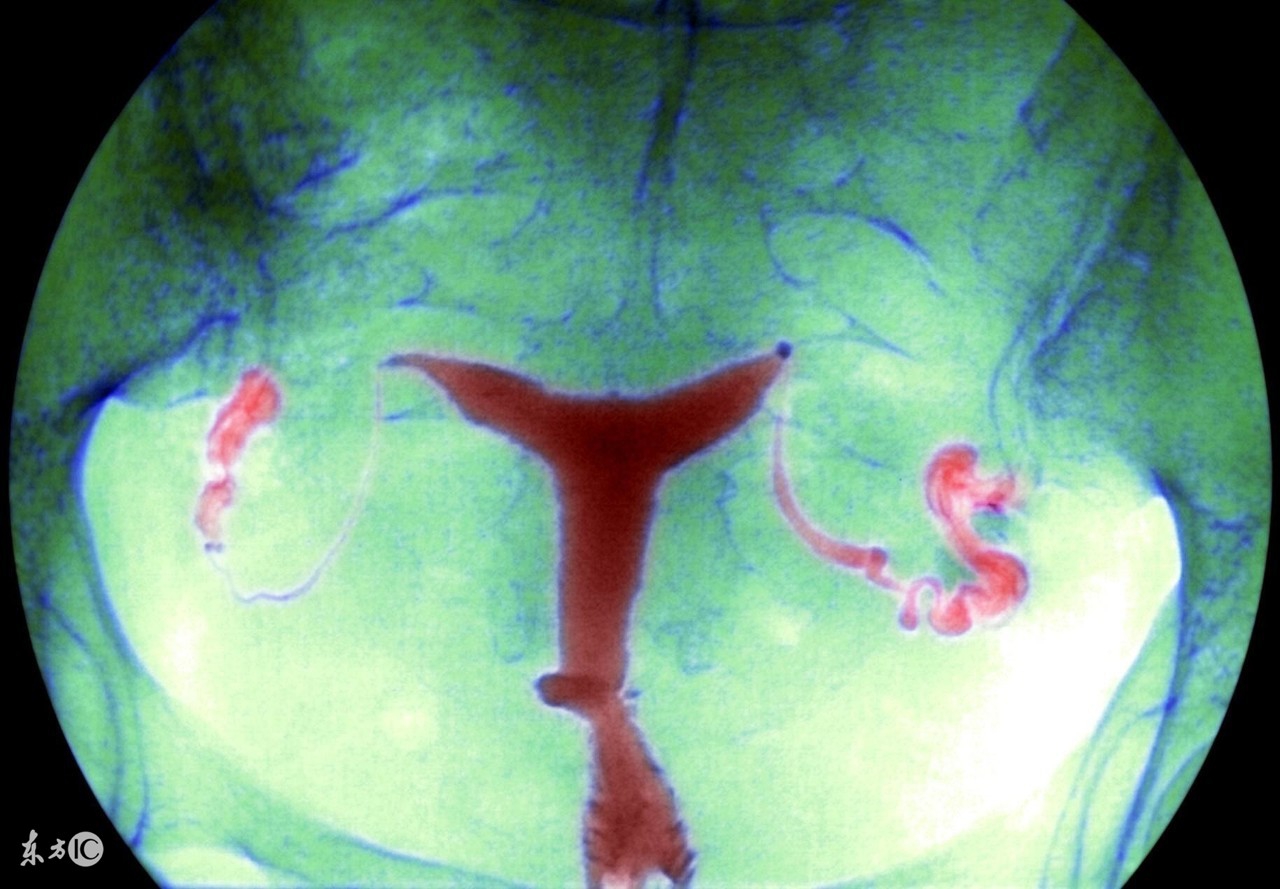

盆腔炎是女性常见的一种疾病,可分为慢性和急性。生活中,慢性盆腔炎比较常见,这种病在病发时可能会伴随着一些低热,病人会觉得自己总是感到劳累,但是由于全身上下的症状并没有很明显,所以难以引起关注。

慢性盆腔炎可能会引起下腹坠痛,这是盆腔出血或者瘢痕粘连导致,特别是在女性在劳累,月经前后情况会有所加剧。在生活中不乏有女性因为慢性盆腔炎的诊治不及时,最后导致了不孕不育。如果想要预防盆腔炎,就需要做到以下几点: